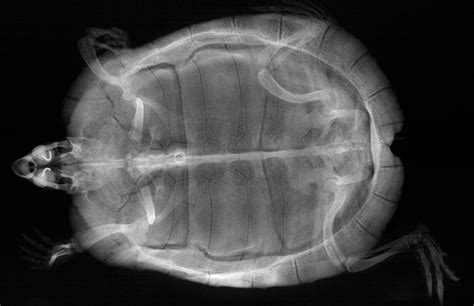

Hey there, fellow turtle enthusiasts ! If you’re a proud parent to one of these amazing shelled creatures, you already know they’re pretty unique pets. But here’s something super important that many new owners might not realize: turtle X-rays are an absolutely critical diagnostic tool for ensuring their long-term health and well-being. Unlike a dog or cat where you can easily spot a limp or a cough, turtles are masters of disguise, often hiding illness until it’s quite advanced. Their very anatomy, that impressive shell, which is part of their skeletal system, makes internal examination incredibly challenging without specialized tools. This is where the magic of veterinary imaging, specifically X-rays, comes into play, offering a non-invasive, yet incredibly detailed, look into their internal world. We’re talking about getting a full picture of their bones, organs, and any potential issues brewing beneath that protective exterior.

Think about it, guys: a turtle’s shell is designed to protect them, making it really difficult for vets to perform a thorough physical examination of their internal organs. You can’t just feel their abdomen for lumps or check their lungs for fluid in the same way you would with a furry friend. This is precisely why turtle X-rays become an indispensable part of their veterinary care . These images allow experienced reptile vets to literally see through the shell and bones, identifying a whole host of problems that would otherwise go undetected until symptoms become severe, and often, much harder to treat. From common ailments like metabolic bone disease (MBD) , which can cause significant skeletal deformities and pain, to more urgent concerns like pneumonia or the presence of foreign bodies in their digestive tract, an X-ray can provide immediate, actionable insights. For female turtles, X-rays are also the go-to method for diagnosing serious conditions like egg binding (dystocia) , a life-threatening situation where eggs get stuck internally. Early detection is truly the name of the game when it comes to reptile health, and X-rays empower veterinarians to catch problems before they spiral out of control. It’s not just about treating illness, but also about offering incredible value in preventative care , allowing vets to monitor bone density, organ size, and overall internal structure over time. Investing in these diagnostic images means investing in a longer, happier, and healthier life for your cherished shelled companion. So, the next time your vet suggests an X-ray for your turtle, understand that they’re recommending one of the most powerful tools available to truly understand what’s happening inside.

Alright, so we’ve established why turtle X-rays are super important, but let’s get down to the nitty-gritty: what exactly can these incredible images show us ? When your turtle undergoes an X-ray, it’s like getting a secret blueprint of their internal architecture, revealing a wealth of information crucial for accurate diagnosis. It’s honestly amazing what a skilled reptile veterinarian can deduce from a few well-positioned radiographs. Let’s break down some of the most common and critical conditions that these powerful turtle X-ray diagnostics can unveil, giving vets the information they need to formulate the best possible treatment plan for your little (or not-so-little) shelled buddy.

One of the most frequent findings on a turtle X-ray is related to bone health , particularly conditions like Metabolic Bone Disease (MBD) . This is a very common issue in captive reptiles, often due to improper diet (lack of calcium or vitamin D3) and inadequate UV light exposure. On an X-ray, MBD can manifest as generalized poor bone density, meaning the bones appear thinner and less opaque than they should. Vets might also observe shell deformities , such as pyramiding or softening, or even fractures that have occurred due to weakened bones. Identifying MBD early through X-rays allows for dietary adjustments and environmental modifications before the condition becomes debilitating. Another critical finding is evidence of respiratory issues , such as pneumonia . Turtles with pneumonia often present with lethargy and nasal discharge, but an X-ray can confirm the presence of fluid or inflammation in the lungs. You might see a hazy or cloudy appearance in the lung fields, or even a consolidation indicating severe infection. This is a very serious condition for turtles, and X-ray confirmation is vital for immediate treatment with appropriate antibiotics.

Then there’s the incredibly common and often life-threatening problem of foreign body ingestion . Turtles, being curious creatures, sometimes eat things they shouldn’t – gravel, plastic pieces, or even small toys. An X-ray is the gold standard for identifying these objects within the digestive tract. Depending on the material, they will appear as opaque structures against the softer tissue. Locating a foreign body is the first step towards deciding on the best course of action, whether it’s monitoring for natural passage, or more often, surgical removal. For female turtles, one of the most urgent conditions identified by turtle X-rays is egg binding (dystocia) . This is when a female turtle is unable to lay her eggs. X-rays clearly show the presence of eggs and their location within the reproductive tract. Vets can assess the number, size, and position of the eggs, which helps them determine if medical intervention (like oxytocin injections) or surgical removal is necessary. Without an X-ray, diagnosing egg binding would be incredibly difficult, often leading to fatal complications.

Furthermore, turtle X-ray imaging can reveal the presence of bladder stones, also known as uroliths . These calcified stones can form in the bladder and cause significant pain and obstruction. On an X-ray, they appear as distinct, dense white structures. Identifying them allows vets to plan for surgical removal, relieving the turtle’s discomfort. Fractures or trauma to the shell or bones, perhaps from a fall or an unfortunate accident, are also clearly visible. X-rays help assess the extent of the damage and guide the repair process. Even tumors or internal masses can sometimes be detected, appearing as abnormal densities or structures within the body cavity. While an X-ray might not provide a definitive diagnosis of cancer, it can indicate the presence of an abnormality that warrants further investigation, like a biopsy or more advanced imaging. It’s truly a testament to the power of this diagnostic tool that so many varied and vital pieces of information can be gathered from a simple, non-invasive image. Understanding these potential revelations allows pet parents to appreciate the depth of information their vet is working with to care for their cherished reptile. So, yeah, when your vet points to those grey and white images, they’re literally decoding your turtle’s internal story!

When reviewing the images, your vet will be looking at various aspects. They’ll examine the bone density of the shell and limbs, noting any signs of metabolic bone disease like thin bones or shell abnormalities. They’ll scrutinize the lung fields for any haziness or fluid that could indicate pneumonia or other respiratory infections. The digestive tract will be carefully inspected for any abnormal densities that suggest a foreign body or severe impaction. For female turtles, the presence and position of eggs will be a key focus when checking for egg binding . They’ll also assess the size and shape of internal organs, looking for any enlargements or unusual masses. The importance of multiple images cannot be overstated here; viewing your turtle from different angles (like the dorsoventral and lateral views we discussed earlier) provides a much more complete picture than a single shot ever could. For example, a shadow that looks like a mass in one view might just be overlapping organs in another, while a distinct foreign body will be clear from multiple perspectives. This comprehensive approach is part of thorough veterinary interpretation .